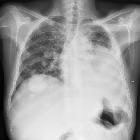

Cannonball metastases refer to multiple large, well-circumscribed, round pulmonary metastases that appear not unsurprisingly like cannonballs. The French terms "envolée de ballons" and "lâcher de ballons", which translate to "balloons release", are also used to describe this same appearance.

Metastases with such an appearance are classically secondary to :